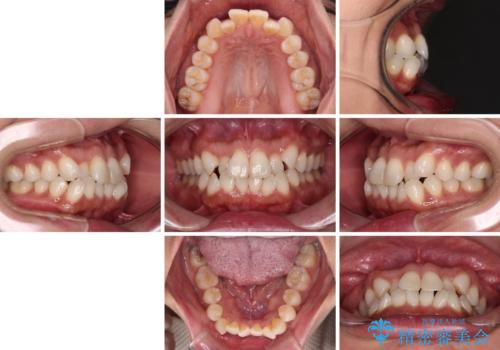

前歯のクロスバイト インビザラインによる矯正治療

- 上下のクロスバイトと前歯のデコボコを気にして来院された患者様です。

インビザラインを用い、IPR(歯と歯の間を削る)と歯列全体を拡大させることで、歯並びを整えていくこととしました。